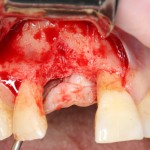

Другой вариант. Имплантируем, но существующего объема костной ткани недостаточно для получения адекватного эстетического и функционального результата:

Поэтому мы используем мембрану Geistlich BioGide и всё ту же аутокостную стружку:

Вот чем мне нравится мембрана BioGide — так это своими свойствами. Предсказуема до мелочей.

Во влажном состоянии она эластична и податлива, поэтому нет необходимости использовать пины или винты:

ну и, швы: